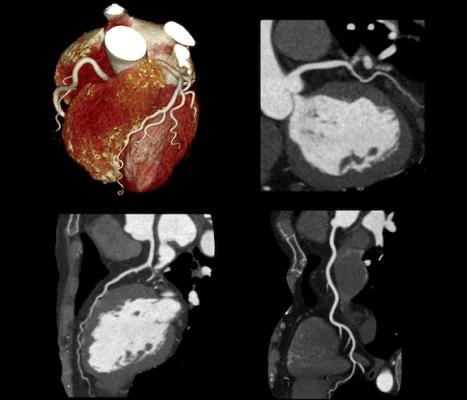

Coronary CT angiography images courtesy of Canon Medical Systems.

According to Leslee Shaw, Ph.D., MSCCT, chair and lead author of the expert consensus: “Coronary computed tomographic angiography (CCTA) provides a wealth of clinically meaningful information. This consensus will serve as a guide given that previously, there has been no uniform agreement on how to identify and quantify the presence or absence of nonobstructive atherosclerosis and high-risk plaque features as precursors for incident coronary events or their use in evidence-based clinical decision-making.”

Growing evidence over the past decade has accumulated regarding the prognostic significance of nonobstructive and obstructive atherosclerotic plaque and its importance for estimating patient risk and guiding preventive care. Rigorous documentation of atherosclerosis on CCTA provides a vital opportunity to make recommendations for preventive care and to initiate and guide an effective care strategy for at-risk patients.